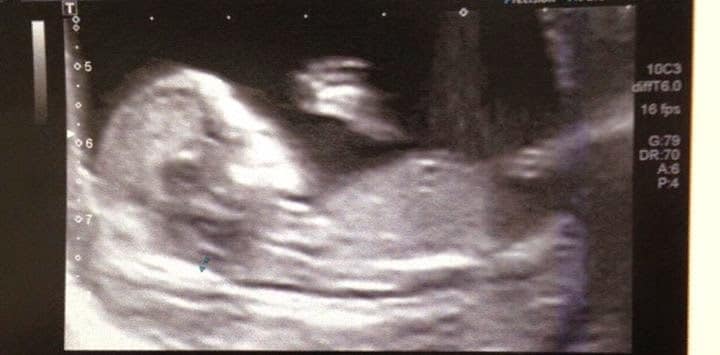

Et voilà la photo de mon bébé à 12 SA et 4 jours le 9 Janvier.

Un petit bébé qui a des mains, qui est bien caché dans mon bidon. Les photos m’ont donné des frissons.